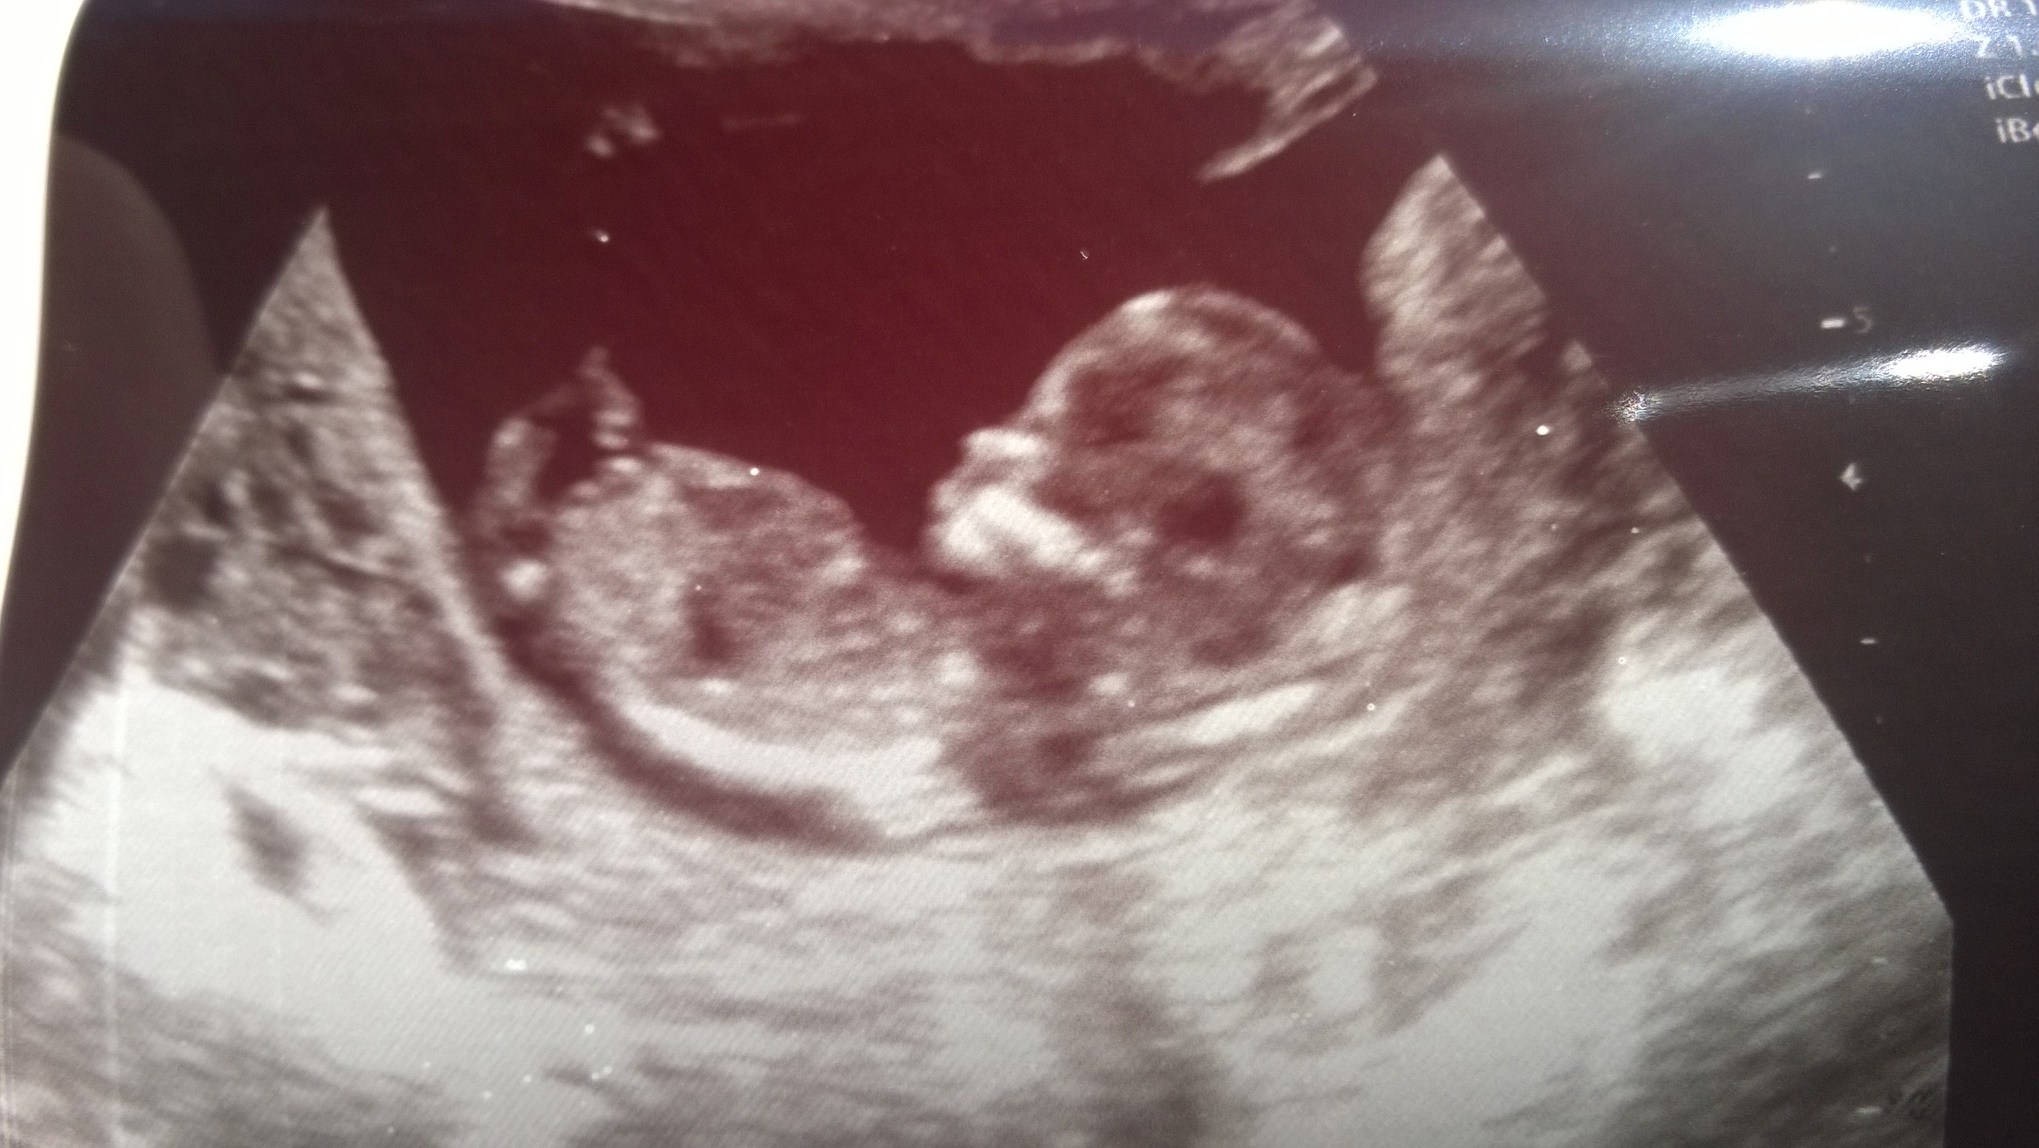

I am bias because it is my new niece or nephew. Looking for some outside opinions. Attachment 19641

Cute :). I don't see a nub either.